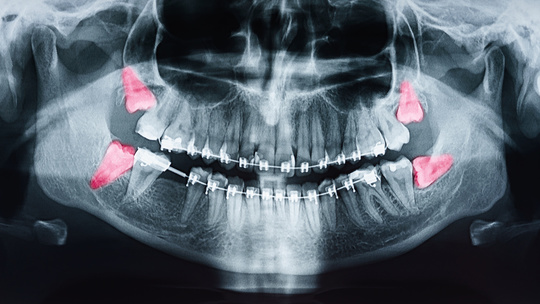

診断

お口の一番奥にあって、萌出してるものや未萌出のものなど赤く表示しました。

まずは、自分の場合、どうなっているのかを正しく知りましょう!

→ 歯科医院で全体を撮る大きなレントゲンと、先生のチェックですぐわかります。